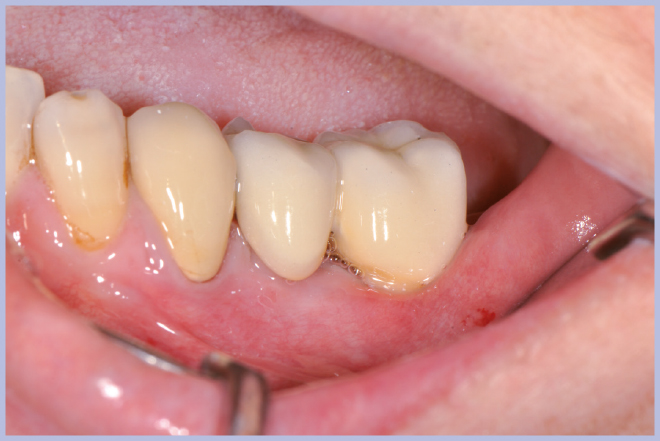

- Figg. 37-40 – Fasi protesiche e finalizzazione con posizionamento di due corone in metallo ceramica

- Fig. 38